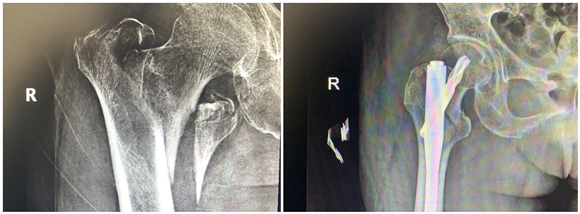

年前,蔡奶奶在家摔了一跤,右側(cè)股骨劇烈疼痛,不能走路,無法動彈。檢查發(fā)現(xiàn)老人右側(cè)股骨粗隆間骨折,當(dāng)時老人拒絕治療,回家臥床后每況愈下。家人不忍心看著老人這么痛苦,了解到該院骨科擅長老年性骨折治療,于是帶著老人來到該院鼓山路院區(qū)骨科就診。來院后,患者診斷為右股骨粗隆間粉碎骨折,并伴有右下肢深靜脈血栓、褥瘡、肺部感染等并發(fā)癥,情況非常危險,此類骨折又稱為“死亡骨折”。據(jù)了解,“死亡骨折”是指老年人的髖部骨折,常常是股骨粗隆間骨折和股骨頸骨折,其中骨折后臥床引起的并發(fā)癥會導(dǎo)致死亡,死亡率高達(dá)40%,又稱人生最后一次骨折。

此類手術(shù)風(fēng)險大,醫(yī)生在告知患者家屬手術(shù)風(fēng)險、術(shù)后康復(fù)、搶救方案等情況后,家屬打消了顧慮,決定盡快給老人家安排手術(shù),擺脫病痛折磨。同時,麻醉科為老人制定了個性化的麻醉方案。王斌手術(shù)團(tuán)隊給患者制定了微創(chuàng)手術(shù)方案,通過三個小孔來進(jìn)行固定,避免了大的手術(shù)切口,整個手術(shù)過程僅僅耗時50分鐘,出血量50ml左右。

患者術(shù)后第二天就下地站立行走,X線顯示骨折對位好,復(fù)查下肢靜脈B超提示少許肌間靜脈血栓。在??漆t(yī)生的康復(fù)指導(dǎo)下,患者褥瘡、肺部感染也很快消失了。術(shù)后第7天,患者康復(fù)出院。